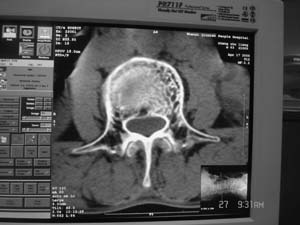

以下是引用余辉在2008-4-27 17:12:00的发言:[br]骨质疏松伴病理性压缩性骨折,椎骨骨松质密度减低,椎体骨小梁稀疏且普遍呈火柴头样改变,椎体无膨胀,无软组织肿块

以下是引用mzh123在2008-4-27 19:33:00的发言:[br]除压缩骨折表现外 还有许莫氏结节改变

以下是引用随光逐影在2008-4-27 21:29:00的发言:[br]除压缩性骨折外,还有许莫氏结节及骨质疏松表现。